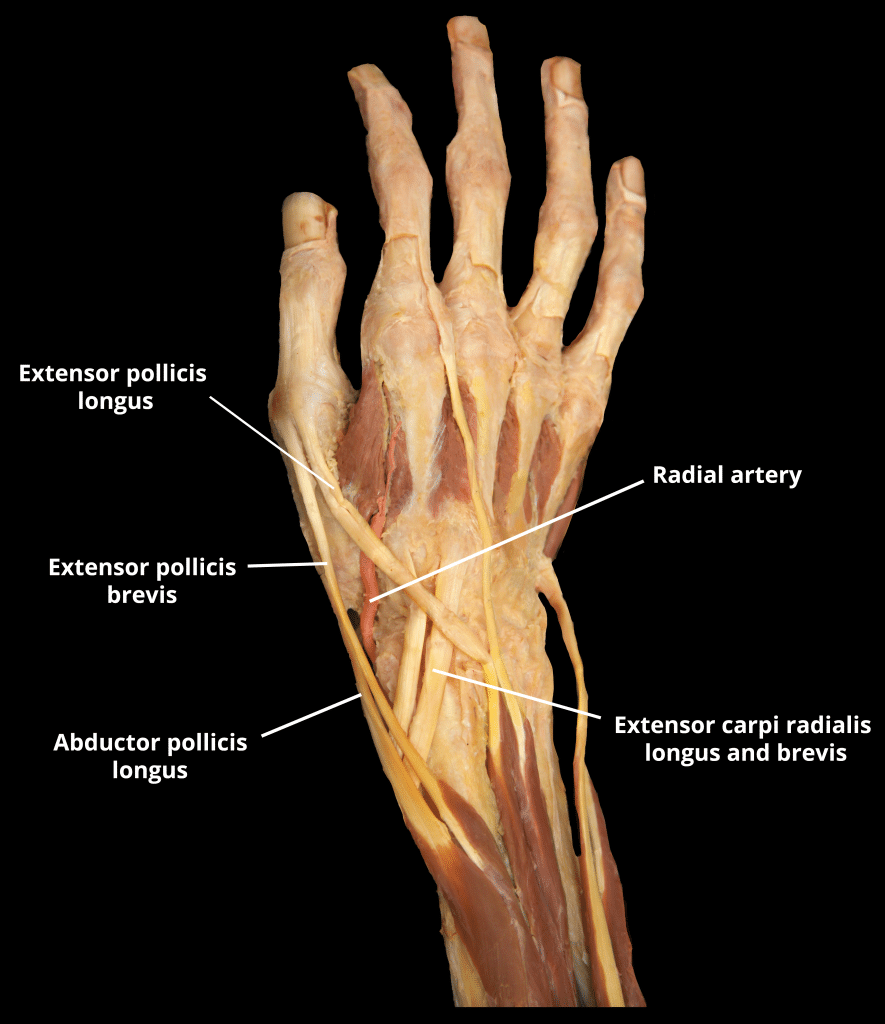

The anatomical snuffbox (also known as the radial fossa), is a triangular depression found on the lateral aspect of the dorsum of the hand. It is located at the level of the carpal bones, and best seen when the thumb is extended. In the past, this depression was used to hold snuff (ground tobacco) before inhaling via the nose – hence it was given the name ‘snuffbox’. In this article, we shall look at the anatomy of the anatomical snuffbox – its borders, contents, and any clinical correlations. By TeachMeSeries Ltd (2025) Fig 1The left anatomical snuffbox. Note its lateral position on the dorsum of the hand Pro Feature - 3D Model You've Discovered a Pro Feature Access our 3D Model Library Explore, cut, dissect, annotate and manipulate our 3D models to visualise anatomy in a dynamic, interactive way. Learn More Borders As the snuffbox is triangularly shaped, it has three borders, a floor, and a roof: Ulnar (medial) border: Tendon of the extensor pollicis longus. Radial (lateral) border: Tendons of the extensor pollicis brevis and abductor pollicis longus. Proximal border: Styloid process of the radius. Floor: Carpal bones; scaphoid and trapezium. Roof: Skin. (Note: The terms medial and lateral are used in the context of the anatomical position, where the forearm is supinated. Take care when describing these borders, as when observing a patient’s anatomical snuffbox, the forearm is usually pronated). It is important to note that the tendons of the muscles form the borders, not the muscles themselves. By TeachMeSeries Ltd (2025) Fig 2The tendinous borders of the anatomical snuffbox. Pro Feature - Dissection Images Borders and contents of the anatomical snuffbox Borders and contents of the anatomical snuffbox You've Discovered a Pro Feature Access our Dissection Image Library Enhance your understanding with high-resolution dissection images showcasing real-life anatomy. Learn More Contents The main contents of the anatomical snuffbox are the radial artery, a branch of the radial nerve, and the cephalic vein: Radial artery – crosses the floor of the anatomical snuffbox, then turns medially and travels between the heads of the adductor pollicis muscle. The radial pulse can be palpated in some individuals by placing two fingers on the proximal portion of the anatomical snuffbox. Superficial branch of the radial nerve – found in the skin and subcutaneous tissue of the anatomical snuffbox. It innervates the dorsal surface of the lateral three and half digits, and the associated area on the back of the hand. Cephalic vein – arises from the dorsal venous network of the hand and crosses the anatomical snuffbox to travel up the anterolateral aspect of the forearm. By TeachMeSeries Ltd (2025) Fig 3Veins of the dorsum of the hand. Cephalic vein highlighted. Clinical Relevance Scaphoid Fracture The scaphoid bone of the hand is the most commonly fractured carpal bone – typically by falling on an oustretched hand (FOOSH). In a fracture of the scaphoid, the characteristic clinical feature is pain and tenderness in the anatomical snuffbox. The scaphoid is at particular risk of avascular necrosis after fracture because of its so-called ‘retrograde blood supply’ which enters at its distal end. This means that a fracture to the middle (or ‘waist’) of the scaphoid may interrupt the blood supply to the proximal part of the scaphoid bone rendering it avascular. Patients with a missed scaphoid fracture are likely to develop osteoarthritis of the wrist in later life. By Gilo1969 (Own work) [CC-BY-SA-3.0], via Wikimedia Commons Fig 4Radiograph of a scaphoid fracture. Adapted from work by Iiibalesiii [CC BY-SA 4.0] Fig 5The blood supply to the scaphoid bone runs from distal to proximal. Do you think you’re ready? Take the quiz below Pro Feature - Quiz The Anatomical Snuffbox Question 1 of 3 Submitting... Skip Next Rate question: You scored 0% Skipped: 0/3 1800 More Questions Available Upgrade to TeachMeAnatomy Pro Challenge yourself with over 1800 multiple-choice questions to reinforce learning Learn More Rate This Article